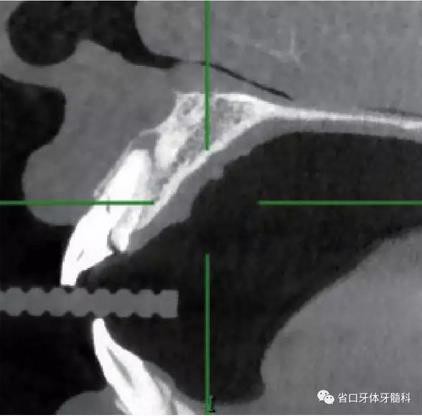

1.?病例簡介 43歲女性患者,主拆:右上前牙松動(dòng)不適數(shù)日要求修復(fù)?,F(xiàn)病史:患者數(shù)年前右上前牙因“齲壞”于外院行根管治療(具體不詳),數(shù)日前牙冠松動(dòng)不適,現(xiàn)覺影響咀嚼及美觀,遂來我院要求進(jìn)一步診治。否認(rèn)高血壓、心臟病等重大疾病,否認(rèn)結(jié)核、肝炎等傳染病史,否認(rèn)手 術(shù)、輸血史等,未發(fā)現(xiàn)藥物過敏。無吸煙習(xí)慣。臨床檢查:口外觀顏面基 本對稱,皮膚無紅腫破潰,顳下頜關(guān)節(jié)區(qū)無彈響、雜音、壓痛,開口度約 37mm,開口型“↓”,頜下、刻下和頸部未及腫大淋巴結(jié)。中位笑線??趦?nèi)檢查,口腔衛(wèi)生可,色素(+),BOP(-),PD=2mm,上頜右側(cè)中切 牙冠部變色,冠根折斷至齦下3mm,叩不適,松動(dòng)Ⅱ°~Ⅲ°。牙齦稍紅, 齦緣水平及齦乳頭高度可,屬于中厚齦生物型,附著齦寬度約5mm,唇系帶附著可。上頜右側(cè)中切牙缺牙間隙與對側(cè)同名牙一致,約>7mm,修復(fù)空 間良好。與對頜牙覆合覆蓋正常。MCT檢查示上頜右側(cè)中切牙冠根折斷至骨 下,根管內(nèi)見充填物,根充不全,根尖見陰影,大小約3mm×3mm。牙槽窩根方可用骨量可,唇側(cè)骨壁完整,冠方骨壁厚度約1mm。

(1)微創(chuàng)拔牙及即刻種植:術(shù)前拍攝口內(nèi)照及實(shí)施牙周基礎(chǔ)治療。常 規(guī)消毒鋪巾阿替卡因局麻下微創(chuàng)拔除上頜右側(cè)中切牙,搔刮拔牙窩及根尖肉 芽組織。探測牙槽骨唇側(cè)骨壁及鄰面牙槽嵴完整,牙齦無撕裂。不翻瓣下于上頜右側(cè)中切牙缺隙近遠(yuǎn)中中點(diǎn)的腭側(cè)牙槽骨及根方定位,按照逐級預(yù)備的原則,緊貼牙槽窩腭側(cè)骨壁制備種植窩洞,植入Zimer®3.7mm×13mm TSV種植體1顆,植入扭矩>35N·cm,以O(shè)sstell測量種植體的ISQ值為68。 種植體平臺(tái)位于唇側(cè)齦緣中點(diǎn)下3mm,與唇側(cè)骨壁內(nèi)側(cè)面形成的跳躍間 隙約2mm,置入Bio-Oss®細(xì)顆粒骨粉0.25g,上愈合基臺(tái)關(guān)閉創(chuàng)口。術(shù)后 CBCT檢查顯示:種植體利用牙槽窩根方骨質(zhì)固位,緊貼牙槽窩腭側(cè)骨壁, 其唇側(cè)面與牙槽窩唇側(cè)骨壁的內(nèi)側(cè)面所形成的跳躍間隙(約2mm)可見顆 粒狀顯影物充填。牙槽窩的唇側(cè)骨壁及唇側(cè)倒凹無缺損穿孔。

圖4 術(shù)前X線片

圖19 術(shù)后MCT